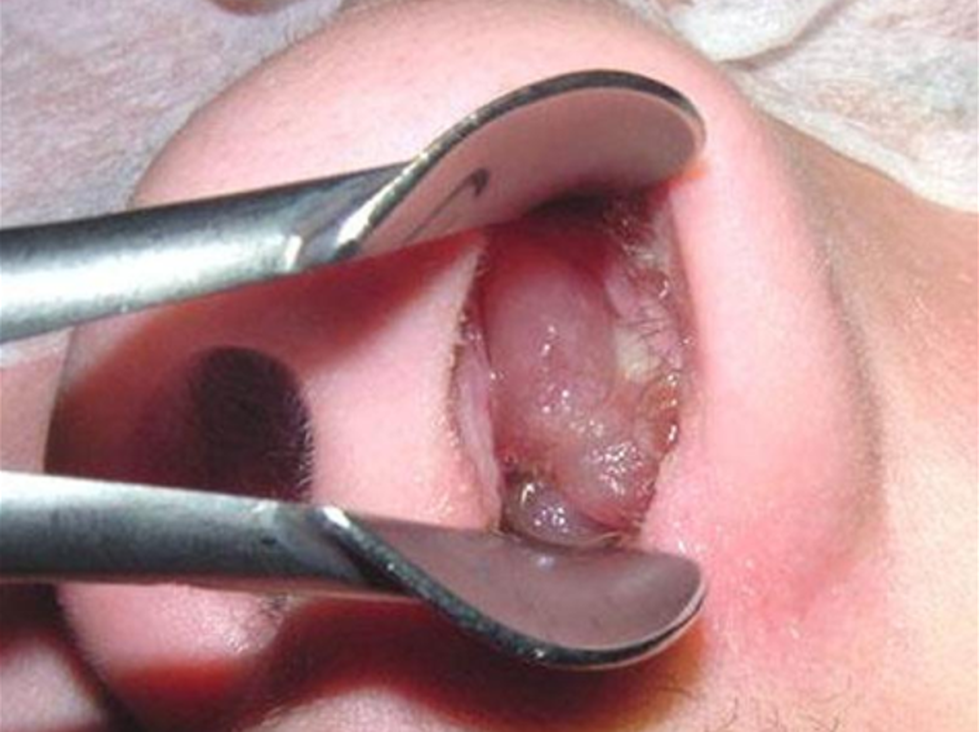

Triệu chứng thực thể: Soi mũi thấy:

- Khối u mềm.

- Tùy theo kích thước của khối polyp mũi, chia làm 4 cấp độ:

Độ I: Polyp mũi khu trú gọn trong phức hợp lỗ ngách.

Độ II: Polyp mũi phát triển ra ngách giữa nhưng chưa vượt quá bờ tự do của cuốn giữa.

Độ III: Polyp mũi vượt quá bờ tự do của cuốn giữa đến lưng cuốn dưới.

Độ IV: Polyp mũi che kín toàn bộ hốc mũi, ra tận cửa mũi sau.